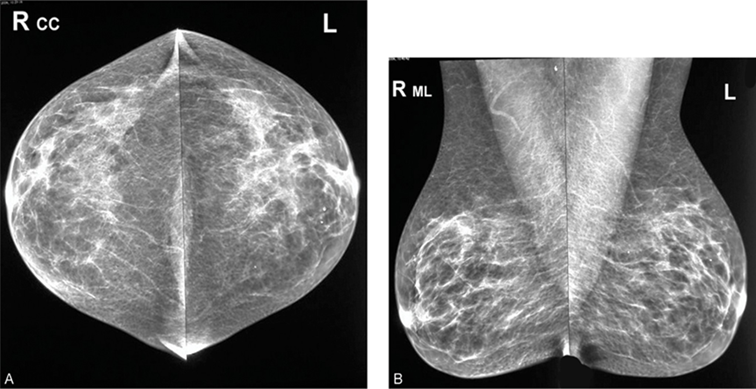

Chụp nhũ ảnh:

Tầm soát và chẩn đoán ung thư vú giai đoạn sớm khi chưa có dấu hiệu lâm sàng.

Hình 10. Chụp nhũ ảnh

- KHÁM VIP: 4+ Chụp Mamography vú (không áp dụng với phụ nữ có thai)